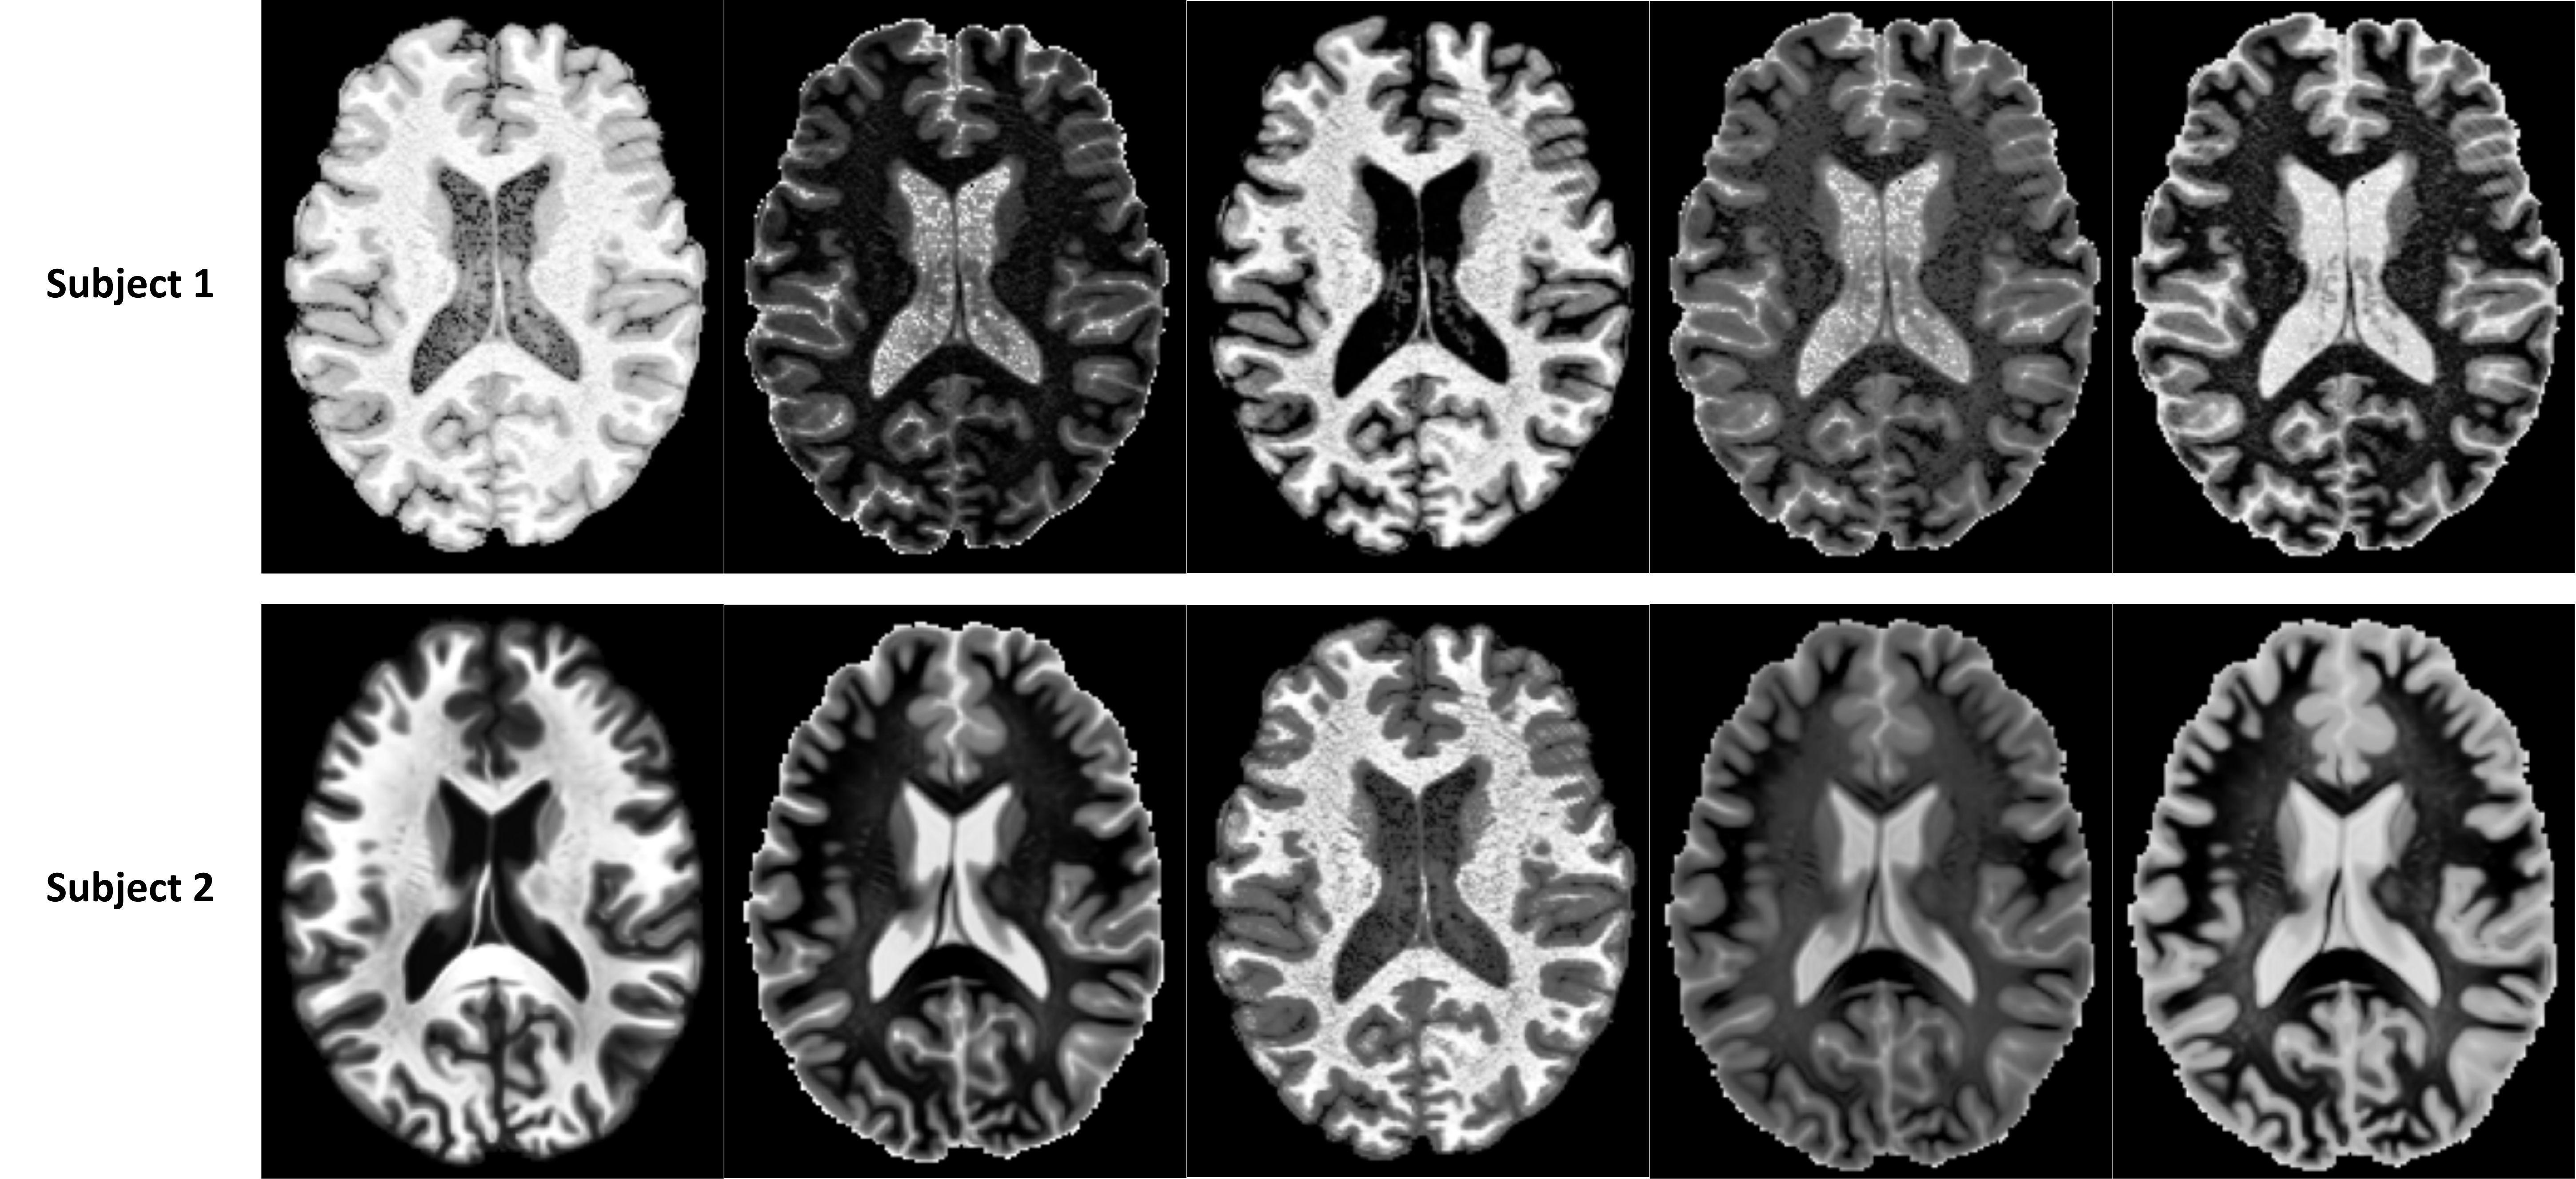

Refer to caption

Figure S2: Axial mid-slices of augmented samples generated using the RC-based contrast augmentation method with 1 ×\times 1 ×\times 1 convolution kernels.

3 Random Convolution-Based Contrast Augmentation

Figure S1 illustrates the model architecture used for random convolution (RC)-based contrast augmentation. The model consists of five non-linear blocks, each comprising an RC layer followed by a LeakyReLU activation. This cascaded design efficiently captures complex and non-linear intensity relationships across various MRI contrasts, generating diverse artificial contrast variations from a single scan. Additionally, Figure S2 presents axial mid-slices of augmented samples generated using the RC-based contrast augmentation scheme. These samples demonstrate the effectiveness of RC in simulating a wide range of artificial contrasts from a single input scan.